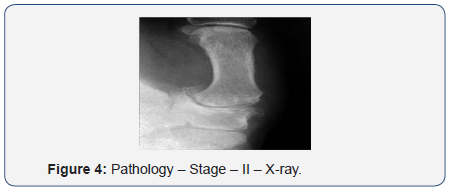

Stage II:

- Severe pain

- Joint space narrowing

- Medial osteophyte (Figures 3 & 4).